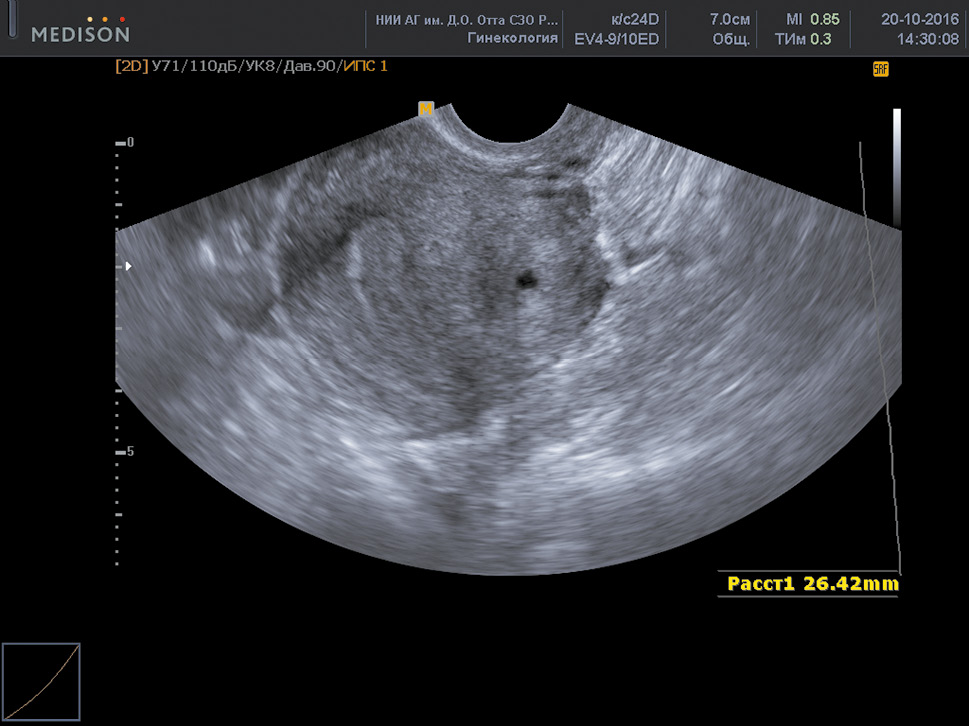

With nodular and focal forms of adenomyosis, the scans reveal the following echographic signs:

- Zones of increased echogenicity of a round or oval shape with smooth contours in the uterine wall with nodular endometriosis, and with uneven contours in case of focal endometriosis.

- Small (2–6 mm in diameter) anechoic inclusions or cystic cavities containing a finely dispersed suspension.

- Increased echogenicity near the proximal edge of the formation and reduced echogenicity near the distal front.

- Closely adjacent bands of medium and low echogenicity in the pathological focus, oriented perpendicular to the scanning plane.

- Deformity of the median uterine echo with the submucosal location of the nodule. The uterine thickness in focal and nodular adenomyosis depends on the size of the pathological formation (Fig. 4).

Fig. 4. Nodular adenomyosis

Рис. 4. Узловая форма аденомиоза